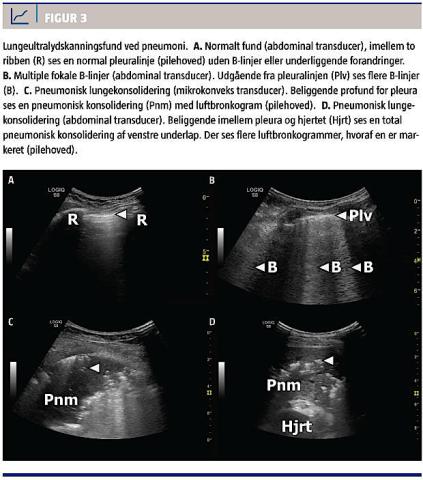

NORMALE FUND

En pneumoni, som udelukkende afficerer dybtliggende dele af lungen og dermed ikke medfører en ændring i densiteten af det lungevæv, som er beliggende lige under pleura viscerale, kan ikke visualiseres med LUS. Pleuralinjen fremtræder normal uden B-linjer, og der er ingen synlige områder med lungekonsolidering (Figur 3A).

FOKALE B-LINJER

Ved en let øget densitet i lungevævet opstår der artefakter, der benævnes B-linjer. En B-linje er en hyperekkoisk, hvid, vertikal linje, der udgår fra pleura og strækker sig usvækket igennem billedet (Figur 3B).

B-linjer er ikke specifikt for pneumoni, da de kan ses både hos raske og ved andre tilstande, der medfører øget densitet i lungen, såsom lungeødem, ARDS og visse interstitielle lungesygdomme. Ved pneumoni er B-linjerne fokalt placeret over det inflammerede område. Pleura kan fremtræde fortykket og fragmenteret. Hvis inflammationen har medført adhærensdannelse imellem pleurabladene, vil der ikke kunne ses lung sliding.

LUNGEKONSOLIDERING

En pneumoni, der har medført konsolidering af lungeparenkymet lige under pleura viscerale, visualiseres direkte med LUS. Den pneumoniske konsolidering fremtræder som et hyperekkoisk, gråt område, der sonomorfologisk kan minde om strukturen i leveren eller milten. Pneumoni er kendetegnet ved et irregulært og uskarpt afgrænset område, hvor der i randzonen ofte forekommer B-linjer. Desuden er det karakteristisk for pneumoni, at der findes luftbronkogrammer (Figur 3C og Figur 3D). Fænomenet kendes også fra røntgen- og CT-billeder og skyldes, at der er luftholdige bronkier i det inflammerede, konsoliderede

lungevæv. Med LUS ses luftbronkogrammer som

hyperekkoiske, hvide linseformede elementer eller som forgreninger inde i konsolideringen. De kan variere i diameter og flytte sig synkront med respirationen [8].

Ved LUS kan lungeemboli, tumor og atelektase sonomorfologisk ligne en pneumonisk konsolidering, men der ses ikke luftbronkogrammer [3].